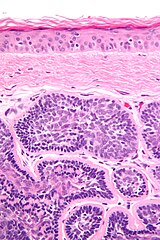

| Micrograph of a dermal cylindroma. H&E stain. | |

In dermatologic pathology, a dermal cylindroma, also dermal eccrine cylindroma or cutaneous cylindroma[1]: 666 ) and (less specifically) cylindroma, is a benign adnexal tumor[2] that occurs on the scalp and forehead.

Multiple cylindromas may grow together in a "hat-like" configuration, sometimes referred to as a turban tumor.[3] Cylindromas are uncommon dysplasias of skin appendages.[4]

They lack of a significant number of lymphocytes; this differentiates them from spiradenomas.

Micrograph of dermal cylindroma in H&E stain.

Dermal cylindroma. Puzzle-like distribution of tumour foci.

Dermal cylindroma. Hyaline droplets visible in lobules.

Dermal cylindroma, micronodular type.